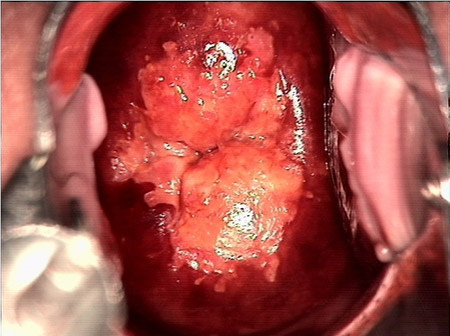

婦科leep錐切手術 CIN2-3

• CIN 2-3CIN 2-3